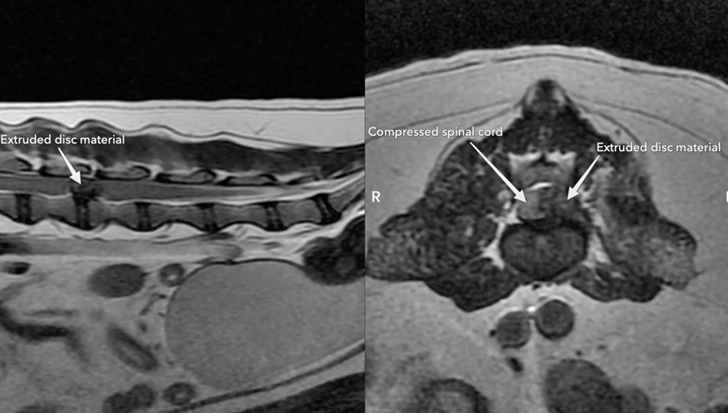

Για τη λεπτομερή απεικόνιση του παρεγχύματος του νωτιαίου μυελού και για τον προσδιορισμό της πλευράς του νωτιαίου μυελού που συμπιέζεται, η μέθοδος επιλογής είναι η μαγνητική τομογραφία. Με την τεχνική αυτή επιτρέπεται, επίσης, η διάγνωση της πρώιμης εκφύλισης του μεσοσπονδύλιου δίσκου πριν την αποτιτάνωση του πηκτοειδή πυρήνα. Στη μαγνητική τομογραφία, στην Τ2-ακολουθία, ο φυσιολογικός πηκτοειδής πυρήνας απεικονίζεται σαν μια ελλειπτική περιοχή με σήμα αυξημένης έντασης και ο ινώδης δακτύλιος με σήμα χαμηλής έντασης, σε αντίθεση με τον εκφυλισμένο πηκτοειδή πυρήνα, που απεικονίζεται με σήμα χαμηλής έντασης και ο διαχωρισμός του από τον ινώδη δακτύλιο δεν είναι εφικτός.

Η μαγνητική τομογραφία έχει επίσης προγνωστική αξία όσον αφορά την εξέλιξη της δισκοκήλης διότι σε θλαστικές κακώσεις αναγνωρίζονται οι περιοχές του παρεγχύματος του νωτιαίου μυελού, που έχει προκληθεί διαταραχή του φραγμού αίματος-νωτιαίου μυελού (απεικόνιση οιδήματος, νέκρωσης, αιμορραγίας). Οι περιοχές αυτές απεικονίζεται στην Τ2-ακολουθία με σήμα αυξημένης έντασης και προδικάζουν δυσμενή πρόγνωση. Σύμφωνα με μια κλινική μελέτη, μόνο το 31% των παραπληγικών σκύλων με απουσία της αίσθησης του βαθύ πόνου και απεικόνιση στην Τ2-ακολουθία μιας περιοχής του νωτιαίου μυελού με σήμα αυξημένης έντασης αποκαταστάθηκε. Αντίθετα, αποκαταστάθηκε το 100% των σκύλων που το παρέγχυμα του ΝΜ δεν είχε αλλοιώσεις ανεξάρτητα από τη διατήρηση ή όχι της αίσθησης του βαθύ πόνου. Η μαγνητική τομογραφία είναι επίσης, η πιο αξιόπιστη μέθοδος για τη διάγνωση της πρόπτωσης υλικού του δίσκου σε μεσοσπονδύλιο τρήμα της αυχενικής μοίρας της σπονδυλικής στήλης.

Οβελιαία και εγκάρσια τομή Τ2 ακολουθίας από ένα παραπληγικό σκύλο. Απεικονίζεται μεγάλη έξοδος πηκτοειδή πυρήνα αριστερά στο μεσοσπονδύλιο διάστημα Ο3-Ο4 που προκαλεί σοβαρή συμπίεση του ΝΜ.